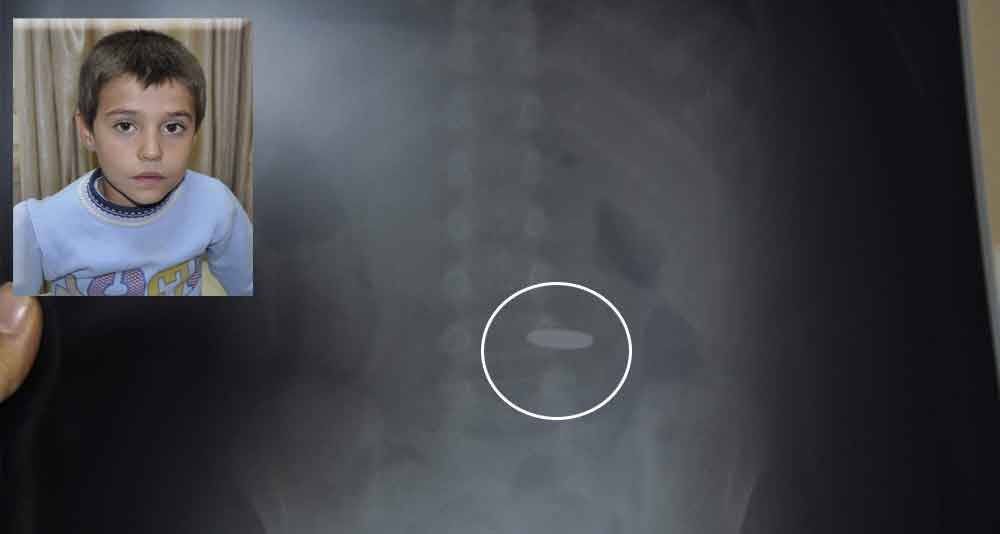

OYUN OYNARKEN PARA YUTTU

Kayseri’de oyun oynarken 50 kuruş yutan küçük çocuk 112 ekipleri tarafından hastaneye kaldırıldı.

Edinilen bilgiye göre Kocasinan ilçesinde Esentepe Mahallesi Sultan Hisar Sokak Manolya Apartmanı’nda meydana gelen olayda 8 yaşındaki H.İ.A.’nın oyun oynadığı sırada 50 kuruşu yuttuğu öğrenildi. Yuttuğu para boğazına takılan küçük H.İ.A. babasının boğazına masaj yapmasıyla parayı ancak yutabildi. Adrese çağrılan 112 ambulansı ile H.İ.A. Kayseri Eğitim ve Araştırma Hastanesi’ne kaldırıldı.

Küçük H.İ.A. Kayseri Eğitim ve Araştırma Hastanesi'ndeki ilk müdahaleden sonra Çocuk Hastanesi'ne sevk edildi.